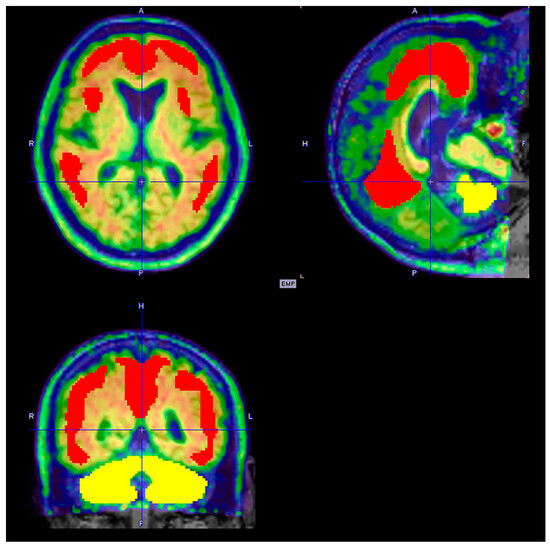

6.2. Brain Amyloid PET

6.2.1. Imaging Data Display [39]

- Gray scale: 18F-florbetaben

- Color (Rainbow): 11C-PiB, 18F-flutemetamol and 18F-NAV4694

- Reverse gray scale: 18F-florbetapir

6.2.2. Image Interpretation for Brain Amyloid PET

Visual Analysis [39,66,67,68]

Negative Scan

Positive Scan

- Findings:

- Visual analysis: The pattern of radiotracer distribution in the bilateral white matter and cerebellum should be discussed. The gray–white matter contrast should be mentioned, and the affected lobe with a loss of gray–white matter contrast should be noted. Abnormal radiotracer uptake in the cerebral cortices or cerebellar cortices, either the same degree and more intense than the white matter uptake, if any, should be described. If present, the degree and location of cerebral atrophy should also be mentioned.

- Quantification analysis (optional): Describe the method used to obtain quantification data (SUVR or Centiloid scale) and the results.